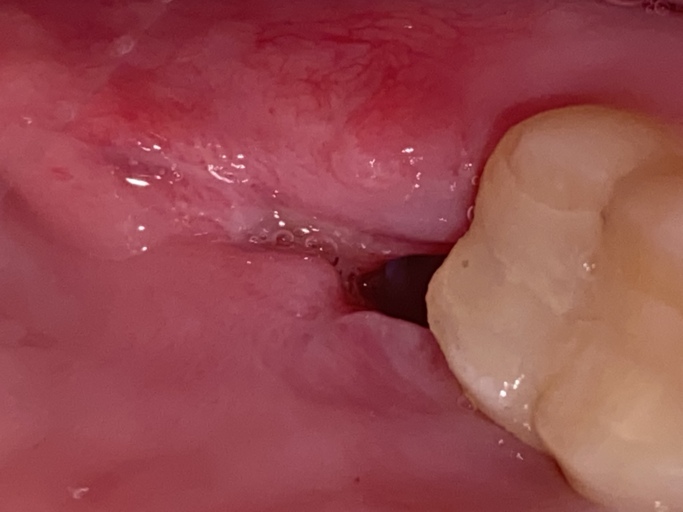

Is wisdom tooth extraction healing okay?

I got a wisdom tooth taken out 6 days ago. It was very impacted, so much so that I had a bone graft put in and stiches as well. I have slight pain which i believe may be from the trauma (it took 30 minutes to get it out) but just want to make sure it is healing properly. The medication they gave helps alleviate the pain and I just finished my course of antibiotics. Does this look like a dry socket?